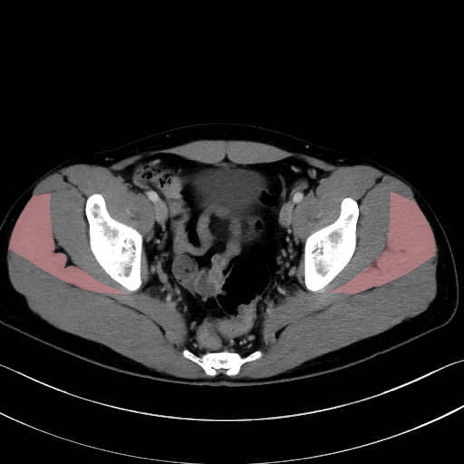

大殿筋 (Gluteus maximus)

中殿筋 (Gluteus medius)

大腿筋膜張筋 (Tensor fasciae latae)